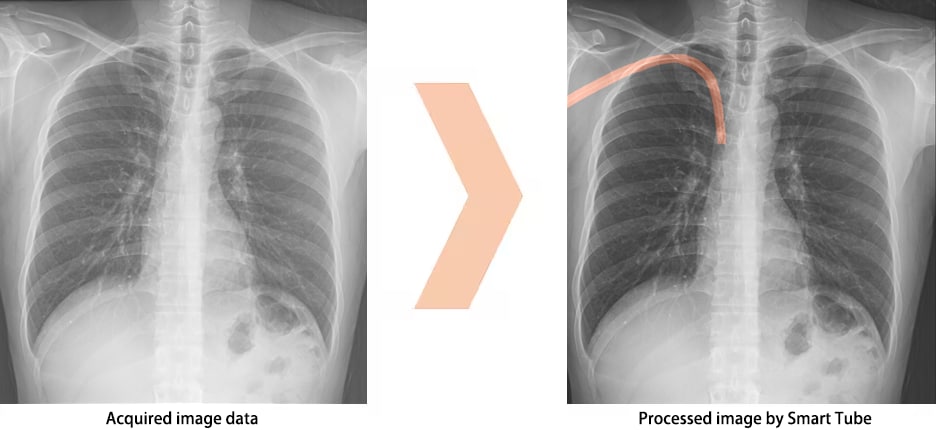

Smart Tube : Tube and Catheter Verification Support Software OPTION

Developed with AI technology, Smart Tube enhances potential areas of tubes and catheters from images, supporting position verification. *1)

Display images processed by Smart DSI *2)

Processed image by Smart Tube

- *1) Do not rely solely on the imaging processing capabilities of Smart Tube when verifying tubes or catheters. Use visual confirmation of images or other methods in reaching a final judgement.

- *2) The AI (artificial intelligence) technology used in Smart Tube is not a self-guided interactive learning-type AI.